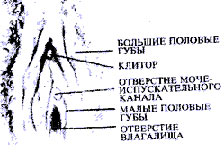

Женские половые органы

Наружные женские половые органы называют вульвой. При возбуждении половые губы наполняются кровью и делают вход во влагалище упругим. Наружные (или большие) половые губы меняют объем и цвет, а внутренние, малые половые губы, сохраняют обычную свойственную им розовую окраску и влажность.

· Осмотрите ваши половые органы с помощью ручного зеркала при хорошем освещении и в удобном положении. Если вы незнакомы со строением половых органов, рисунки помогут вам определить их различные части. Не тревожьтесь, если ваши половые органы выглядят иначе, чем показано на рисунке. Подобно вашим чертам лица и строению тела, они уникальны и значительно варьируют у женщин в размерах, форме, цвете и конфигурации.

· После этого начинайте пальцевое исследование всей области половых органов. Вы уже различаете клитор, который расположен впереди, где соединяются малые половые губы. Однако чтобы его рассмотреть должным образом, нужно оттянуть назад кожную складку, которая его прикрывает. Клитор открывается в виде небольшого розового выступа длиной около полудюйма. Прикасайтесь к нему нежно, так как он очень чувствителен.